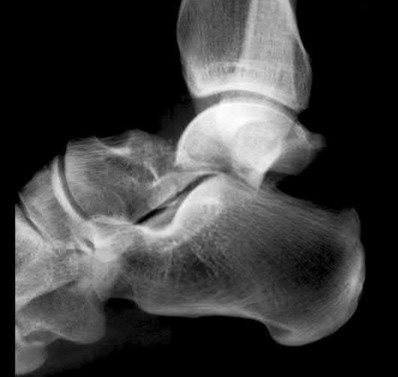

A 25-year-old male sustains an ankle fracture dislocation and undergoes open reduction and internal fixation. He returns to clinic five months following surgery complaining of continued ankle pain and instability with weight bearing. His immediate post-operative AP radiograph is seen in Figure A. Which of the following could have prevented this patient from developing persistent pain?

The patient presents with continued ankle pain and instability following open reduction and internal fixation. The radiograph in figure A demonstrates inadequate restoration of fibular length, likely leading to continued tibiotalar instability.

Illustration A demonstrates fibular malreduction with dislocation of the fibula anterior to the tibial incisura. Illustration B shows a comminuted fibula fracture along with a measurement of length from an intact fibula. The arc from the lateral process of the talus to the peroneal groove of the distal fibula is known as the "dime" sign and should remain unbroken if fibular length has been restored. Illustration C demonstrates the use of a push-pull screw and lamina spreader to regain length intraoperatively for a comminuted fibula fracture.

Chu and Weiner review management of malunions of the distal fibula. The authors state that restoration of fibular length, alignment and rotation leads to reduction of the talus, provides a buttress to talar motion in the setting of an incompetent deltoid, and allows the syndesmotic ligaments to heal at the appropriate tension.